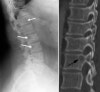

척추종양의 영상 검사

- X-ray

① Lytic lesion : 추체는 50% 이상 파괴되어야 병변이 나타나므로 조기 진단에 도움 X

② Winking owl sign : 전이성 병변에서 특징적으로 전후면 사진상 척추경의 음영이 없어지는 것